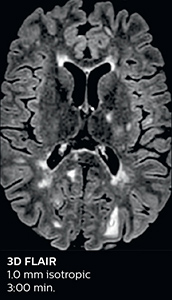

This is an example of acute ischemic stroke with distal occlusion of the right posterior cerebral artery. Note the improved visibility of the ischemic territory on the diffusion weighted image with high b-value. The 3D FLAIR shows a distal PCA occlusion. The fast SWIp depicts the thrombus on the isolated second echo image. The total scan time (including SmartBrain, preparations and a fast 3D T1w TSE Gd) is 8:00 minutes.